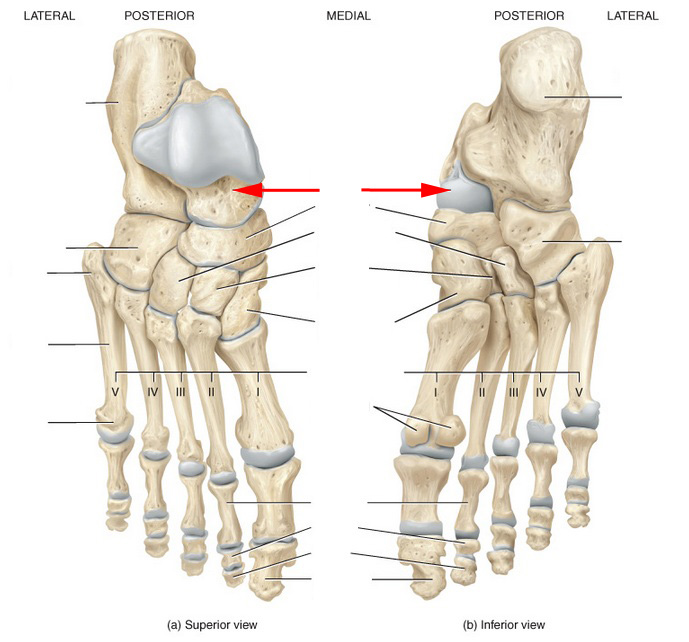

Анатомия фибулы: Подробные фотографии и схемы